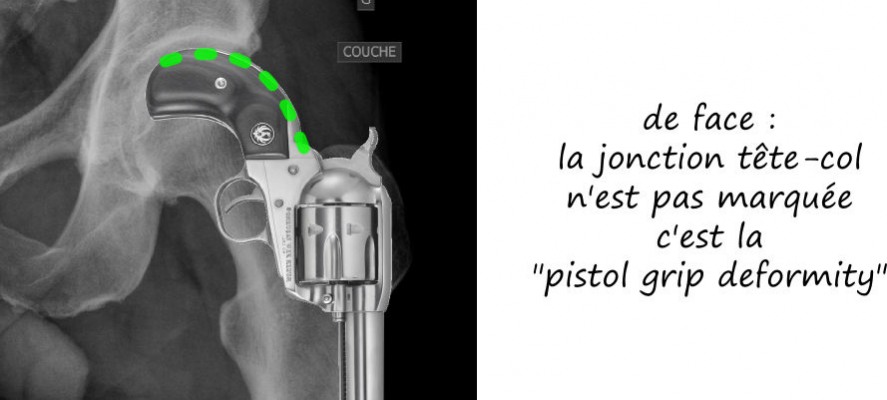

Radiologie standard

Le conflit fémoro acétabulaire se décèle sur de simples radiographies de la hanche, notemment sur le profil de DUNN qui expose la face antérieure du col fémoral. Sur cette radio est estimée l’angle alpha, correpondant à l’angle formé par l’axe du col fémoral et une droite passsant par le centre de la tete fémorale et le point de décrochage de la jonction tete-col, et qui est normalement de l’ordre de 45°; il est augmenté dans les conflits par effet came, comme sur cette radio ci dessous.